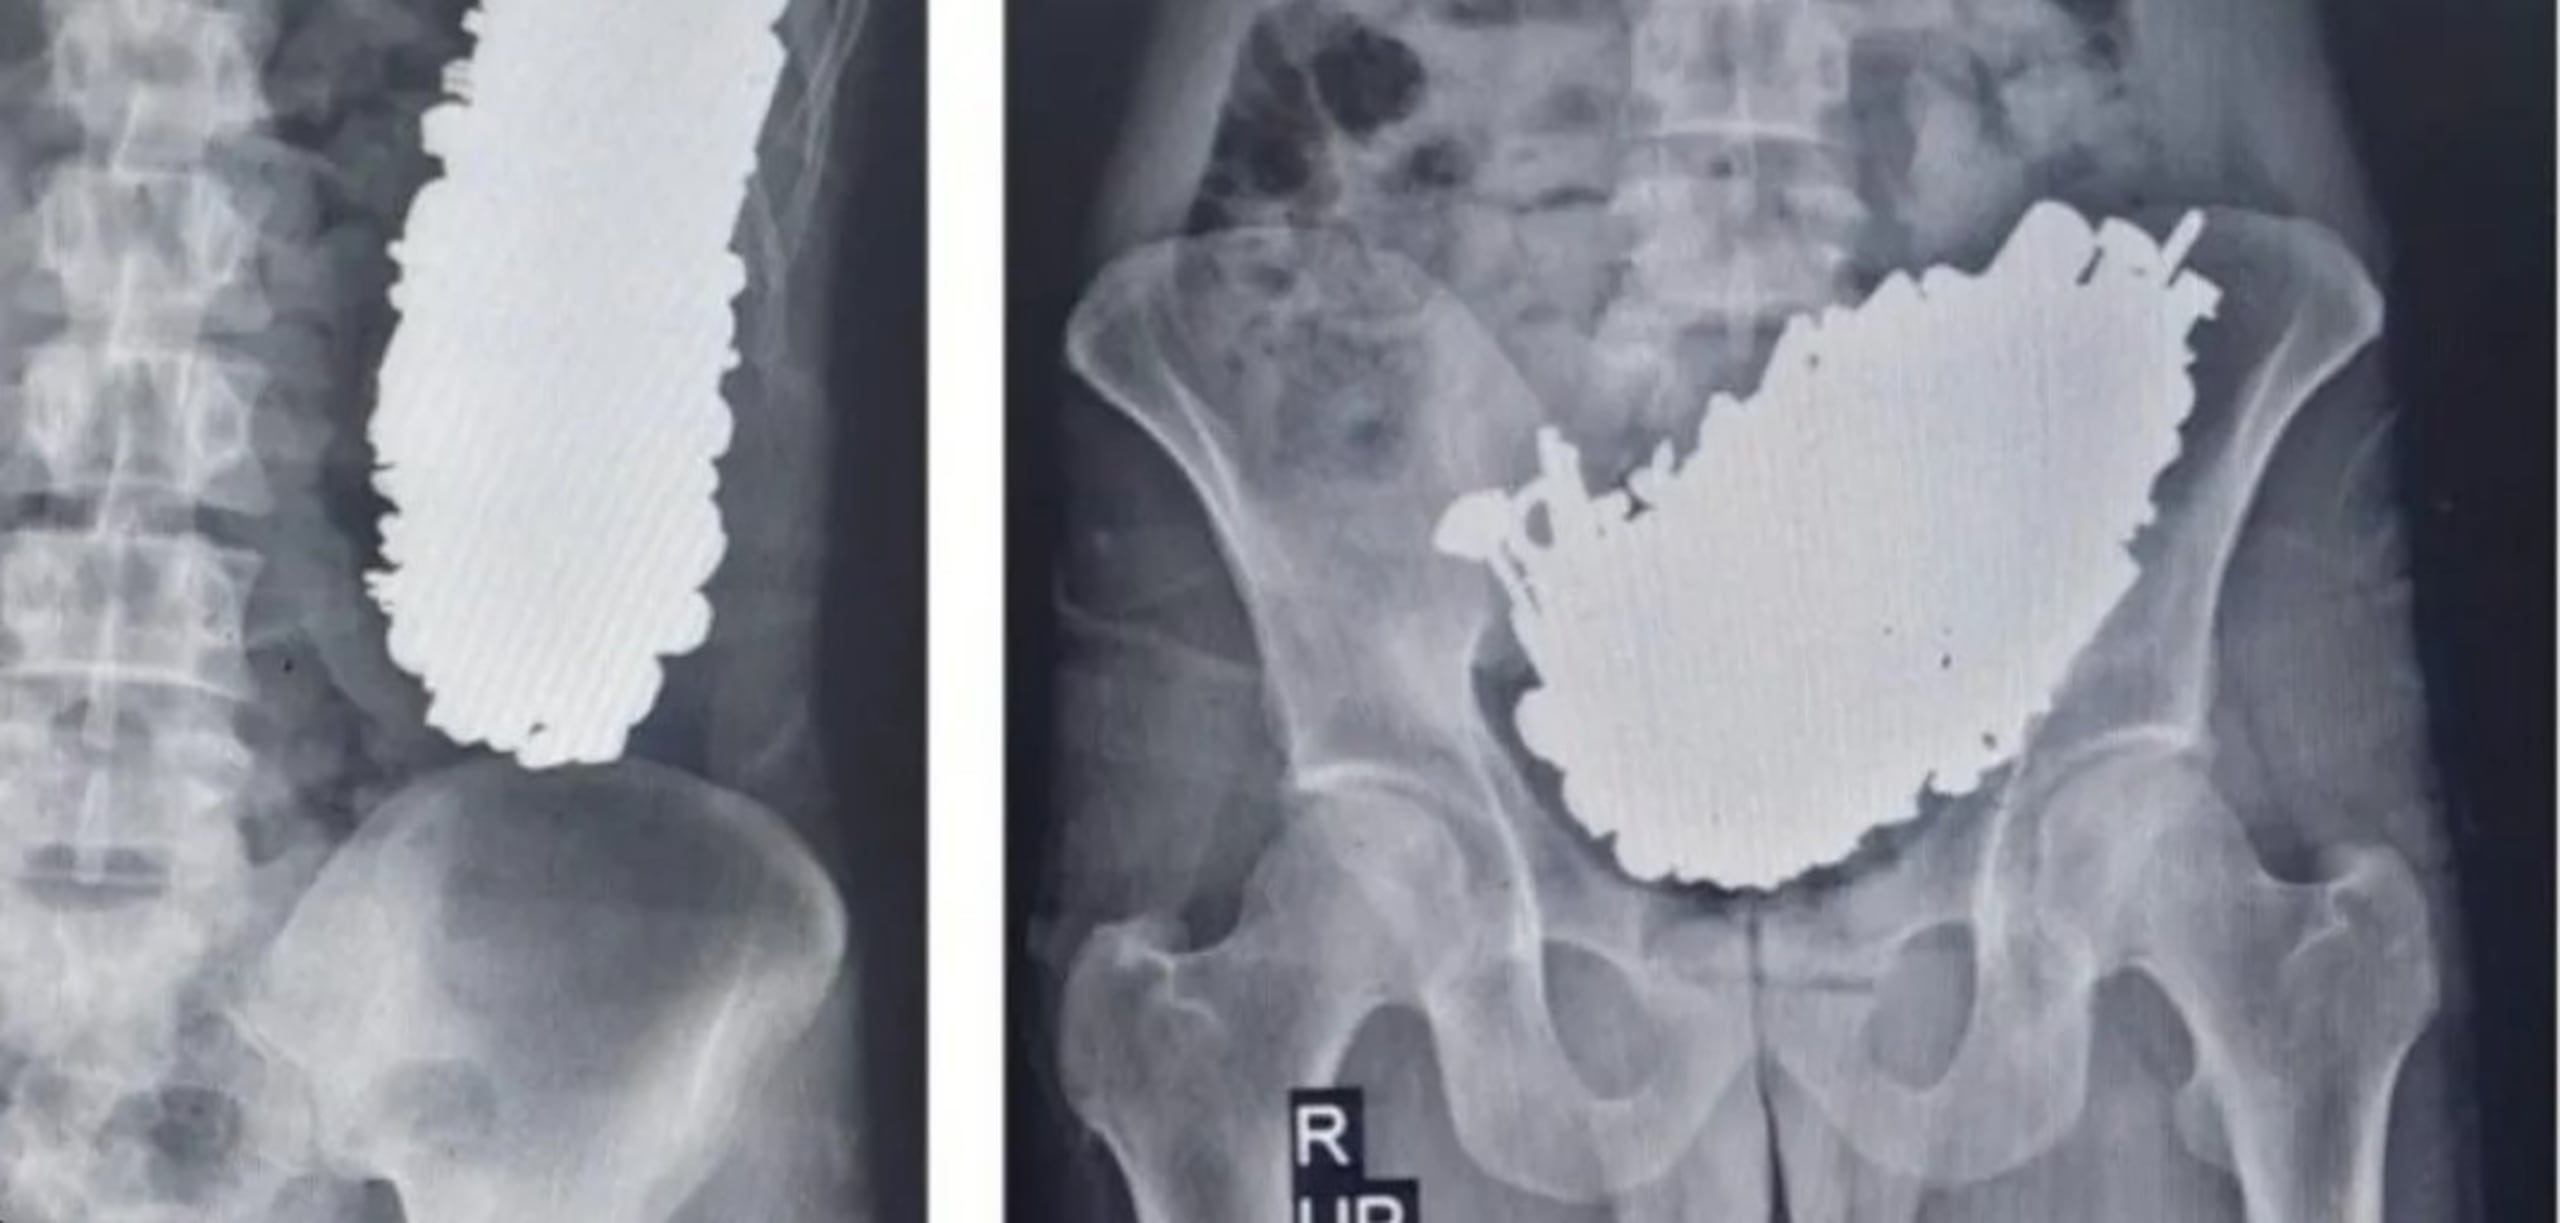

Un grupo de médicos extrajeron 452 objetos metálicos del cuerpo de un hombre de 36 años. Los médicos del hospital Imam Jomeini, en Ahvaz, Irán, explicaron que el hombre fue al hospital quejándose por un dolor abdominal crónico, vómitos frecuentes e intolerancia a líquidos y alimentos.

Los acompañantes del hombre mencionaron que tres meses atrás había ingerido piezas metálicas, por lo que los médicos ordenaron que se hiciera exámenes de radiografía y endoscopia. Luego de hacer los estudios médicos encontraron múltiples objetos metálicos que provocaron la obstrucción gástrica en el paciente.

A pesar de ello tenía signos vitales estables y estaba consciente. En total le extrajeron 452 tornillos, llaves, piedras y otras piezas metálicas, que sumaban un peso de 2.9 kilos.